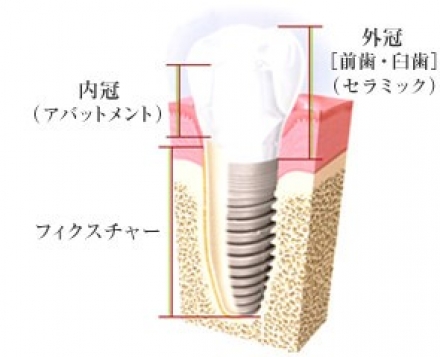

かみ合わせの回復について